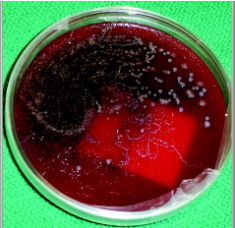

diagnosis of strongyloides stercoralis

Look for rhabditiform larvae in concentrated fecal specimens

Must differentiate from hookworm larvae

Very rarely will you ever see eggs

Would indicate hyper-infection

May see "trails" on your stool culture agar plates--result of migrating larvae from the stool thru the bacterial colonies